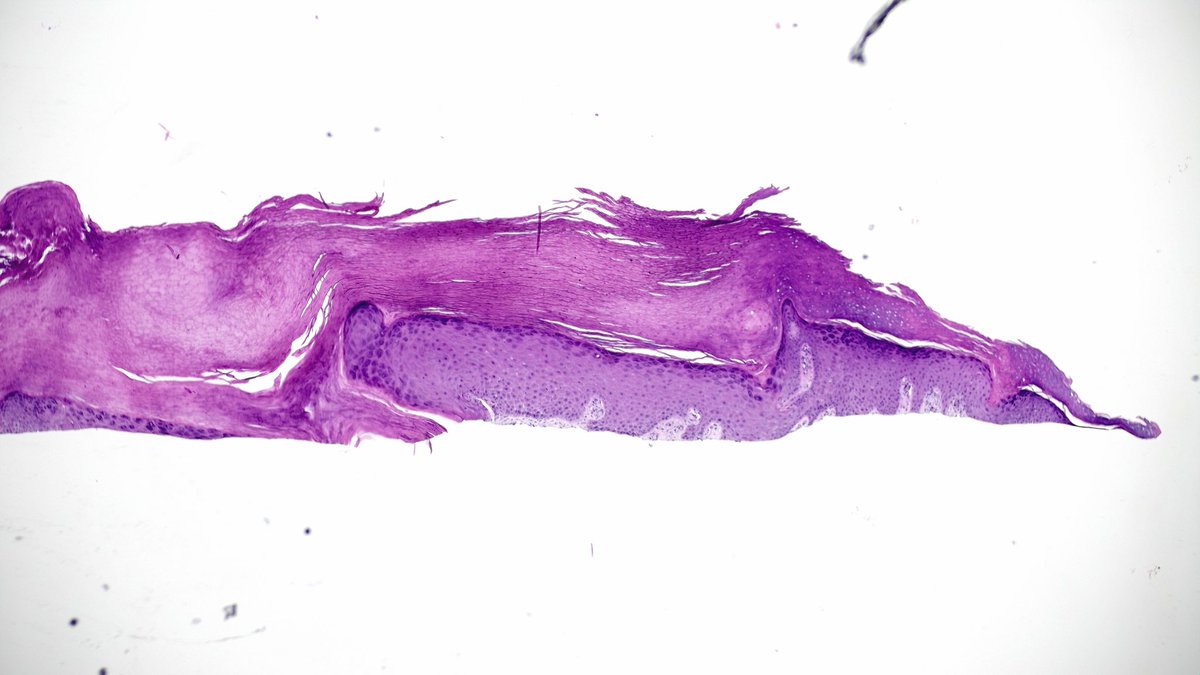

Calf. Elderly. Dx’s welcomed.

>70yo thigh. Eryrhematous nodule with hyperkeratotic scale. @mccalmo @HENRYY_MD Neg for CD34, sox10, cd30 (cd30 bc history said LyP, later found out it’s an autopopulate error). Focal cutaneous mucinosis? Cells are odd though.